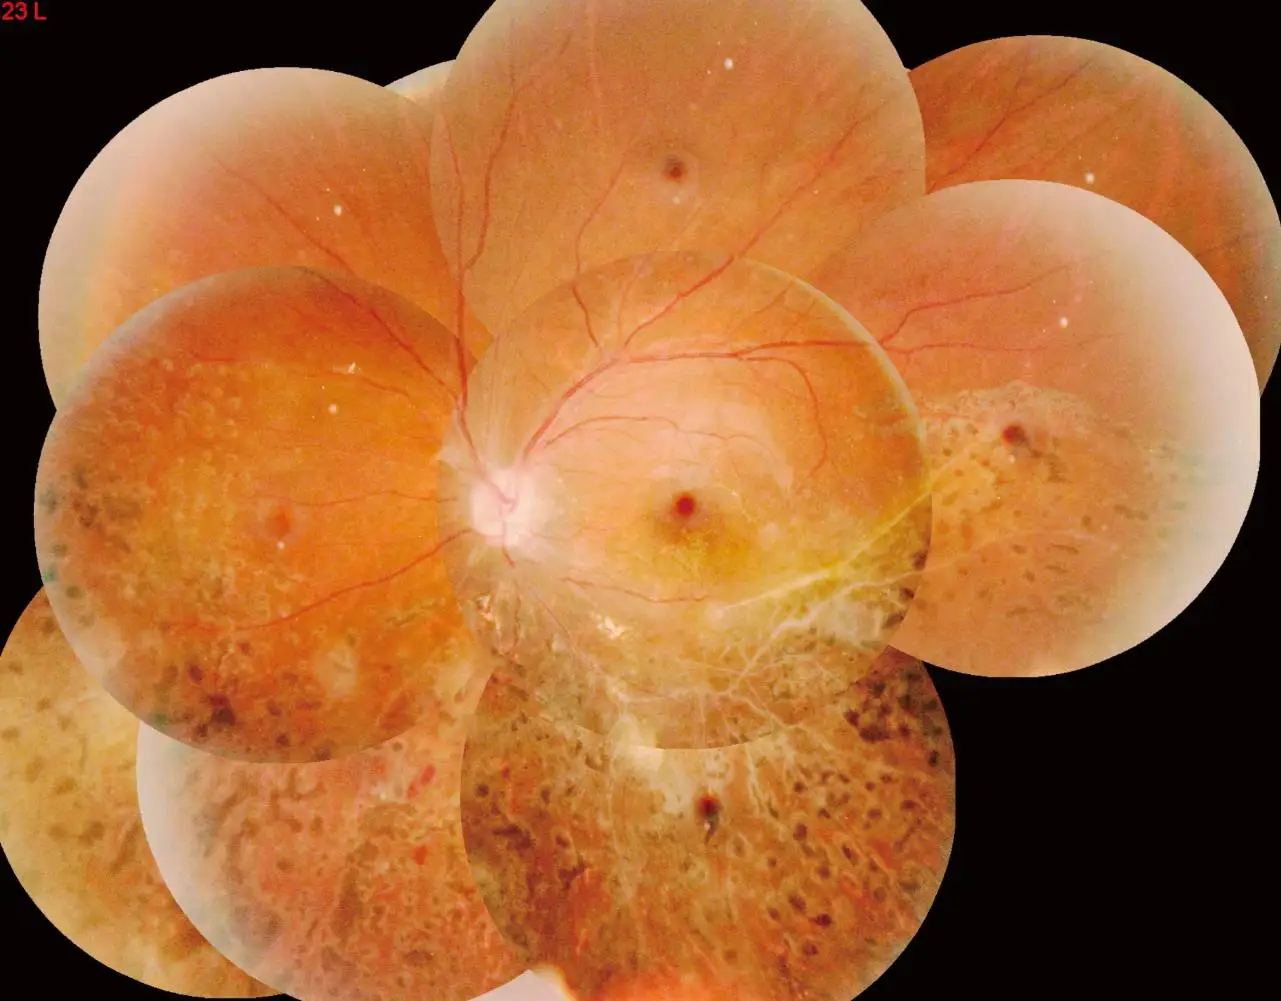

Function | Color fundus | Color fundus | |

Field Of View | Up to 53° | Up to 53° | |

Mosaic | Auto | ||